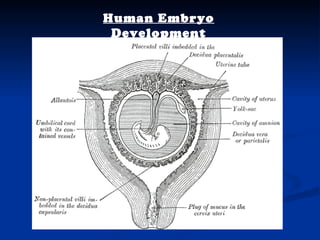

The document discusses embryonic development in humans. It begins with fertilization and cleavage, followed by gastrulation where the three germ layers are formed. During this time the primitive streak and Henson's node develop. Organogenesis then occurs, forming individual organs from the germ layers. Mammalian development includes the allantois and notochord. In humans, the placenta forms and gestation occurs over three trimesters, with major organ structures present by the first trimester.